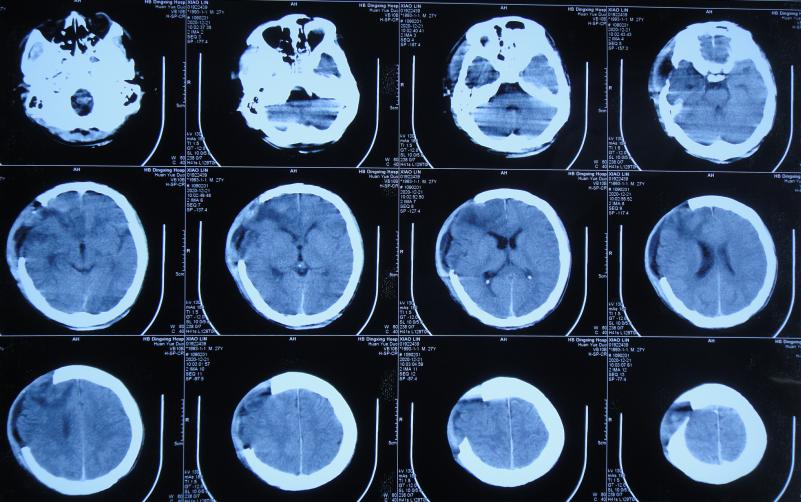

开颅术后次日,出现发热的症状,开颅术后3天即2020年12月15日,拔除了头颅引流管,头颅CT示仍水肿,稍有脑膨出( 图-3 )。

图-3: 2020年12月15日头颅CT